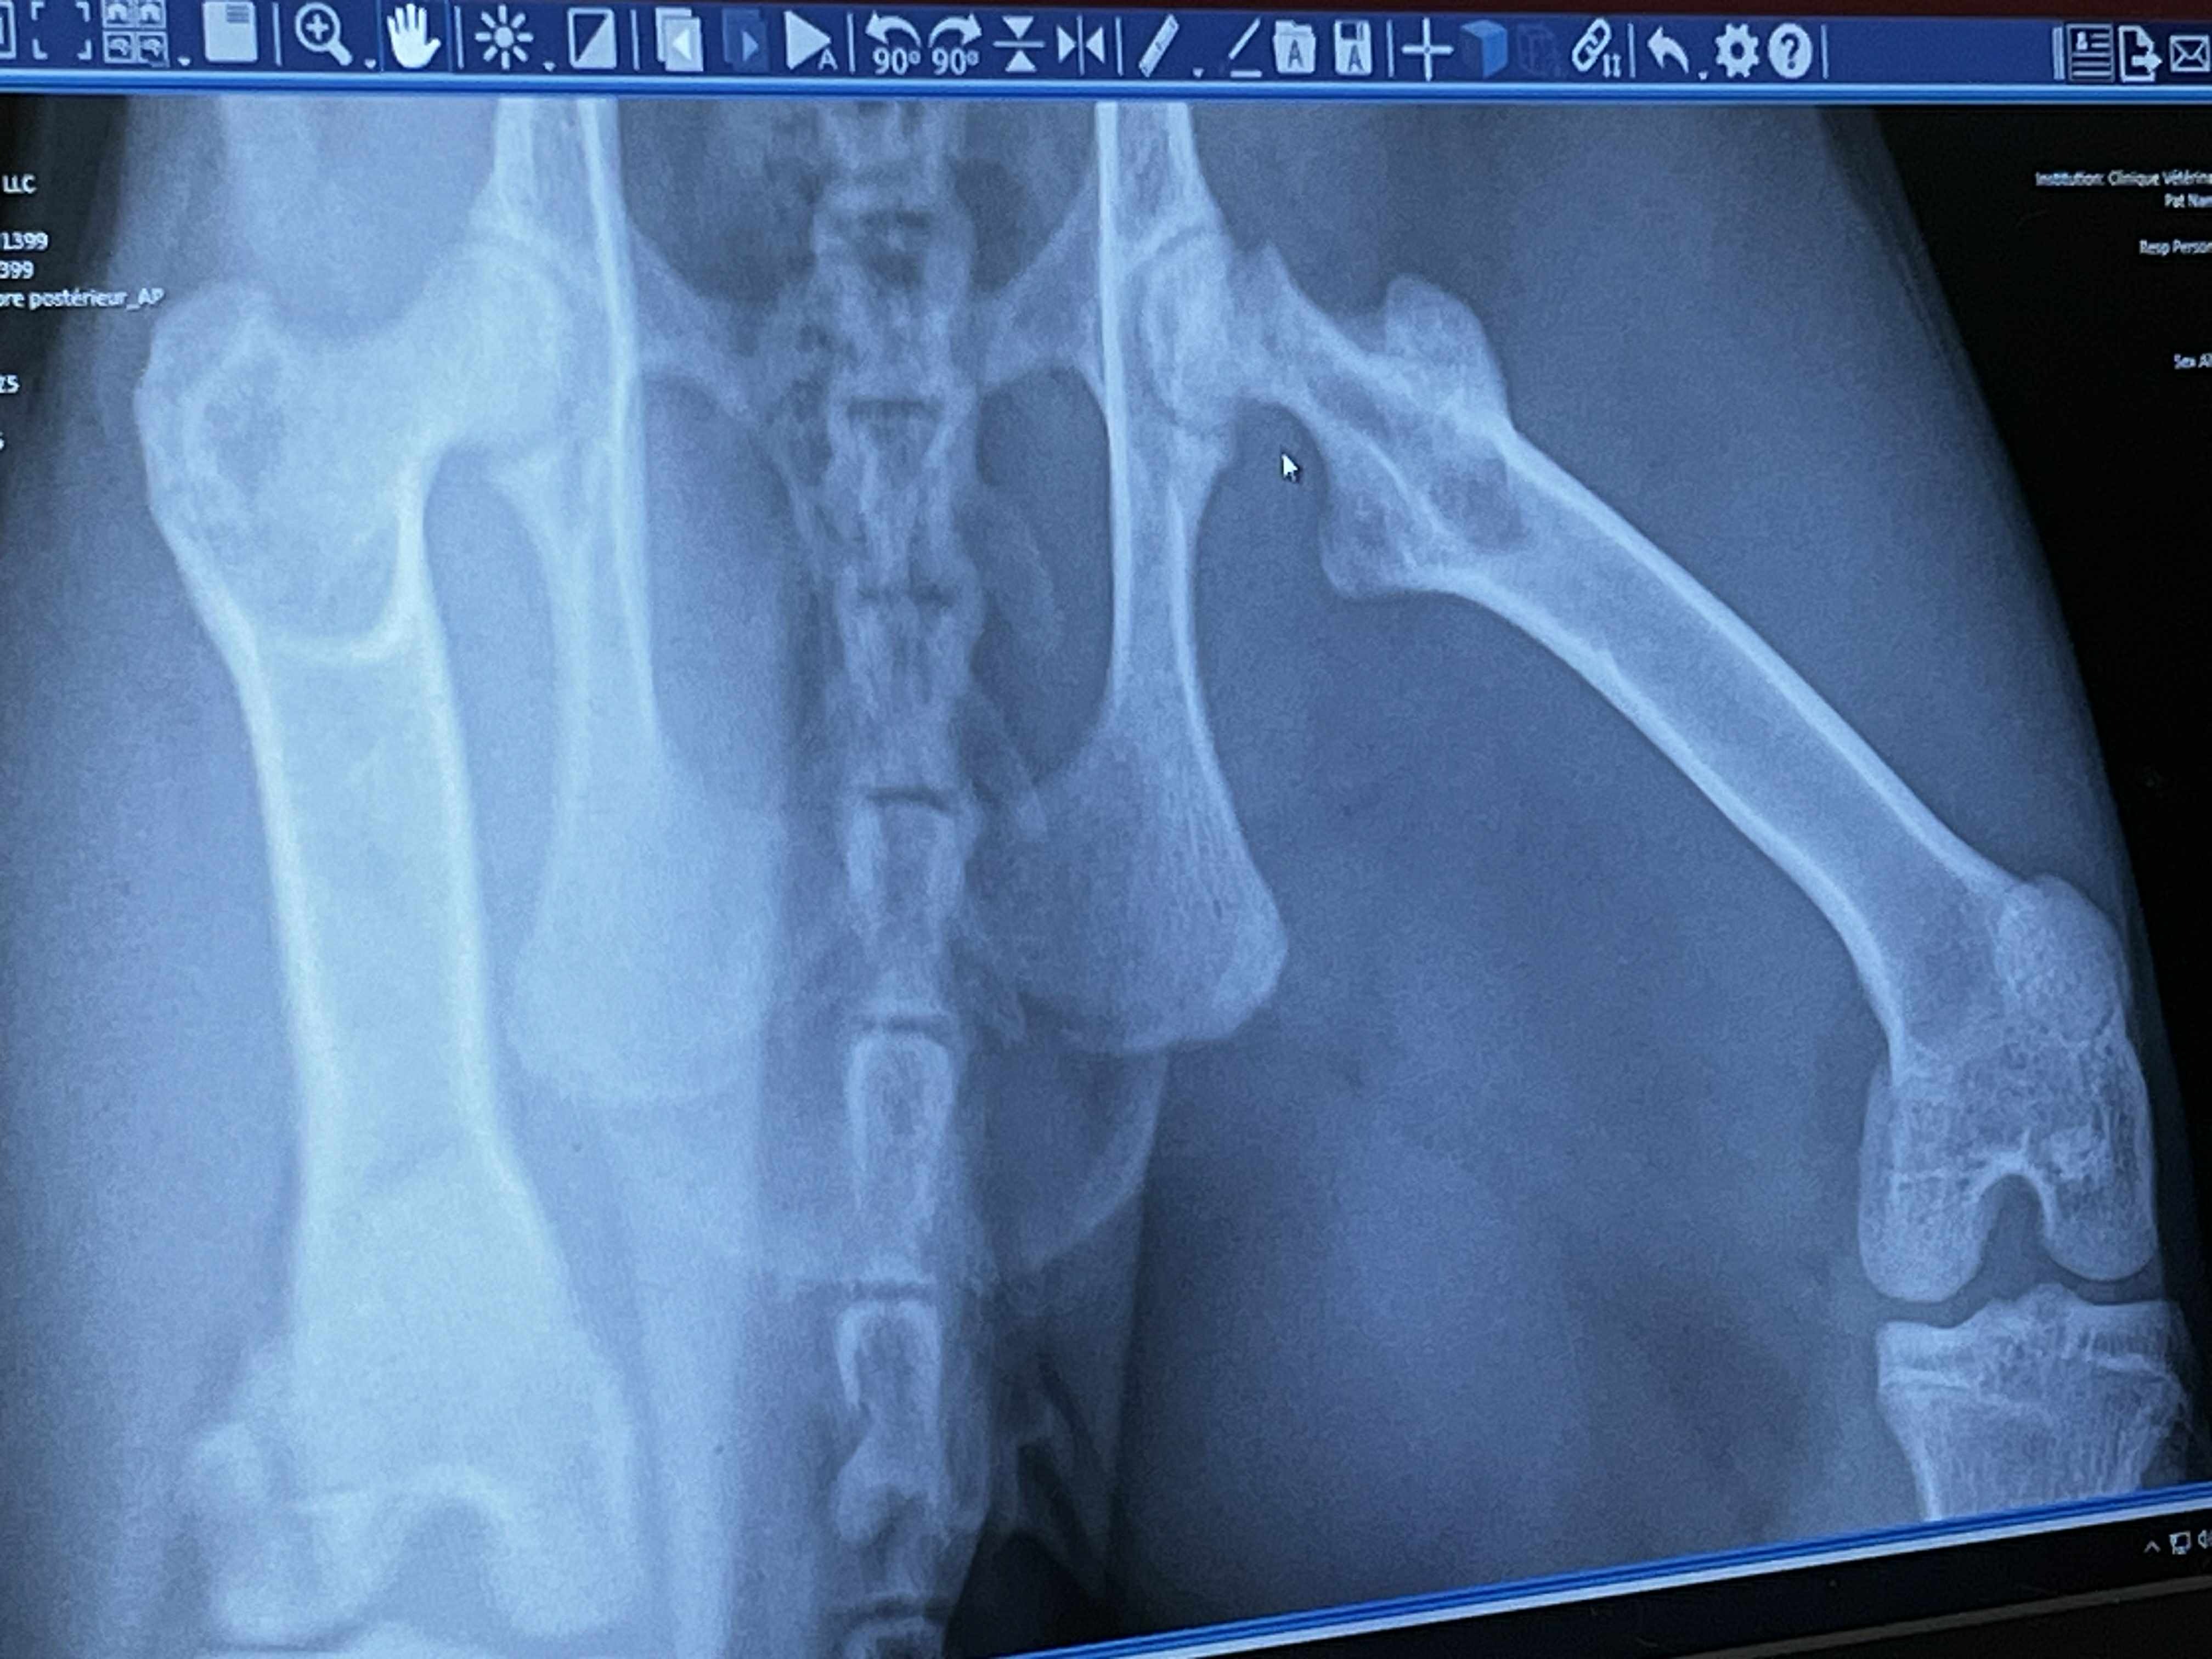

Notre jeune chat, Mochi, s’est fracturé le fémur et requiert une lourde opération pour récupérer. C’est pourquoi, dans l’espoir de permettre à Mochi de vivre sa vie de chat enjoué, nous avons décidé de lancer un GoFundMe. Vous vous en doutez, dans notre monde d’aujourd’hui, les soins vétérinaires sont parfois si chers qu’ils en deviennent inaccessibles. Le prix de son opération s’élève à presque 2900 $, une somme imprévue que mon partenaire et moi aurons du mal à débourser à juste nous deux…

Pour le moment, Mochi ne peut même plus se déplacer seul.